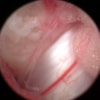

関節鏡検査を実施いたしました。関節鏡検査では、重度の滑膜炎および前十字靭帯の完全断裂が認められました。半月板に損傷は認められませんでした。

関節穿刺を行い、好中球はなく、少数のマクロファージや滑膜細胞が認められるました。膝蓋骨脱臼および前十字靭帯断裂による退行性の関節炎を疑い、関節鏡検査を実施いたしました。関節鏡検査では、重度の滑膜炎および前十字靭帯の完全断裂が認められました。内外側とも半月板に損傷は認められませんでした。